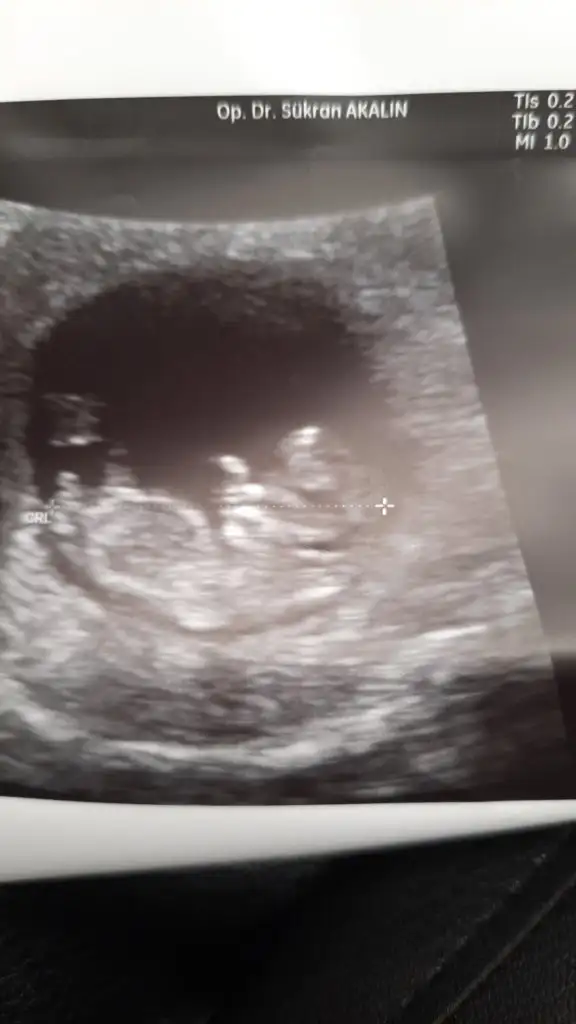

Atmıştım kuzum tekrar atayım

• IMG-20220907-WA0000.webp

15,5 KB · Görüntüleme: 65